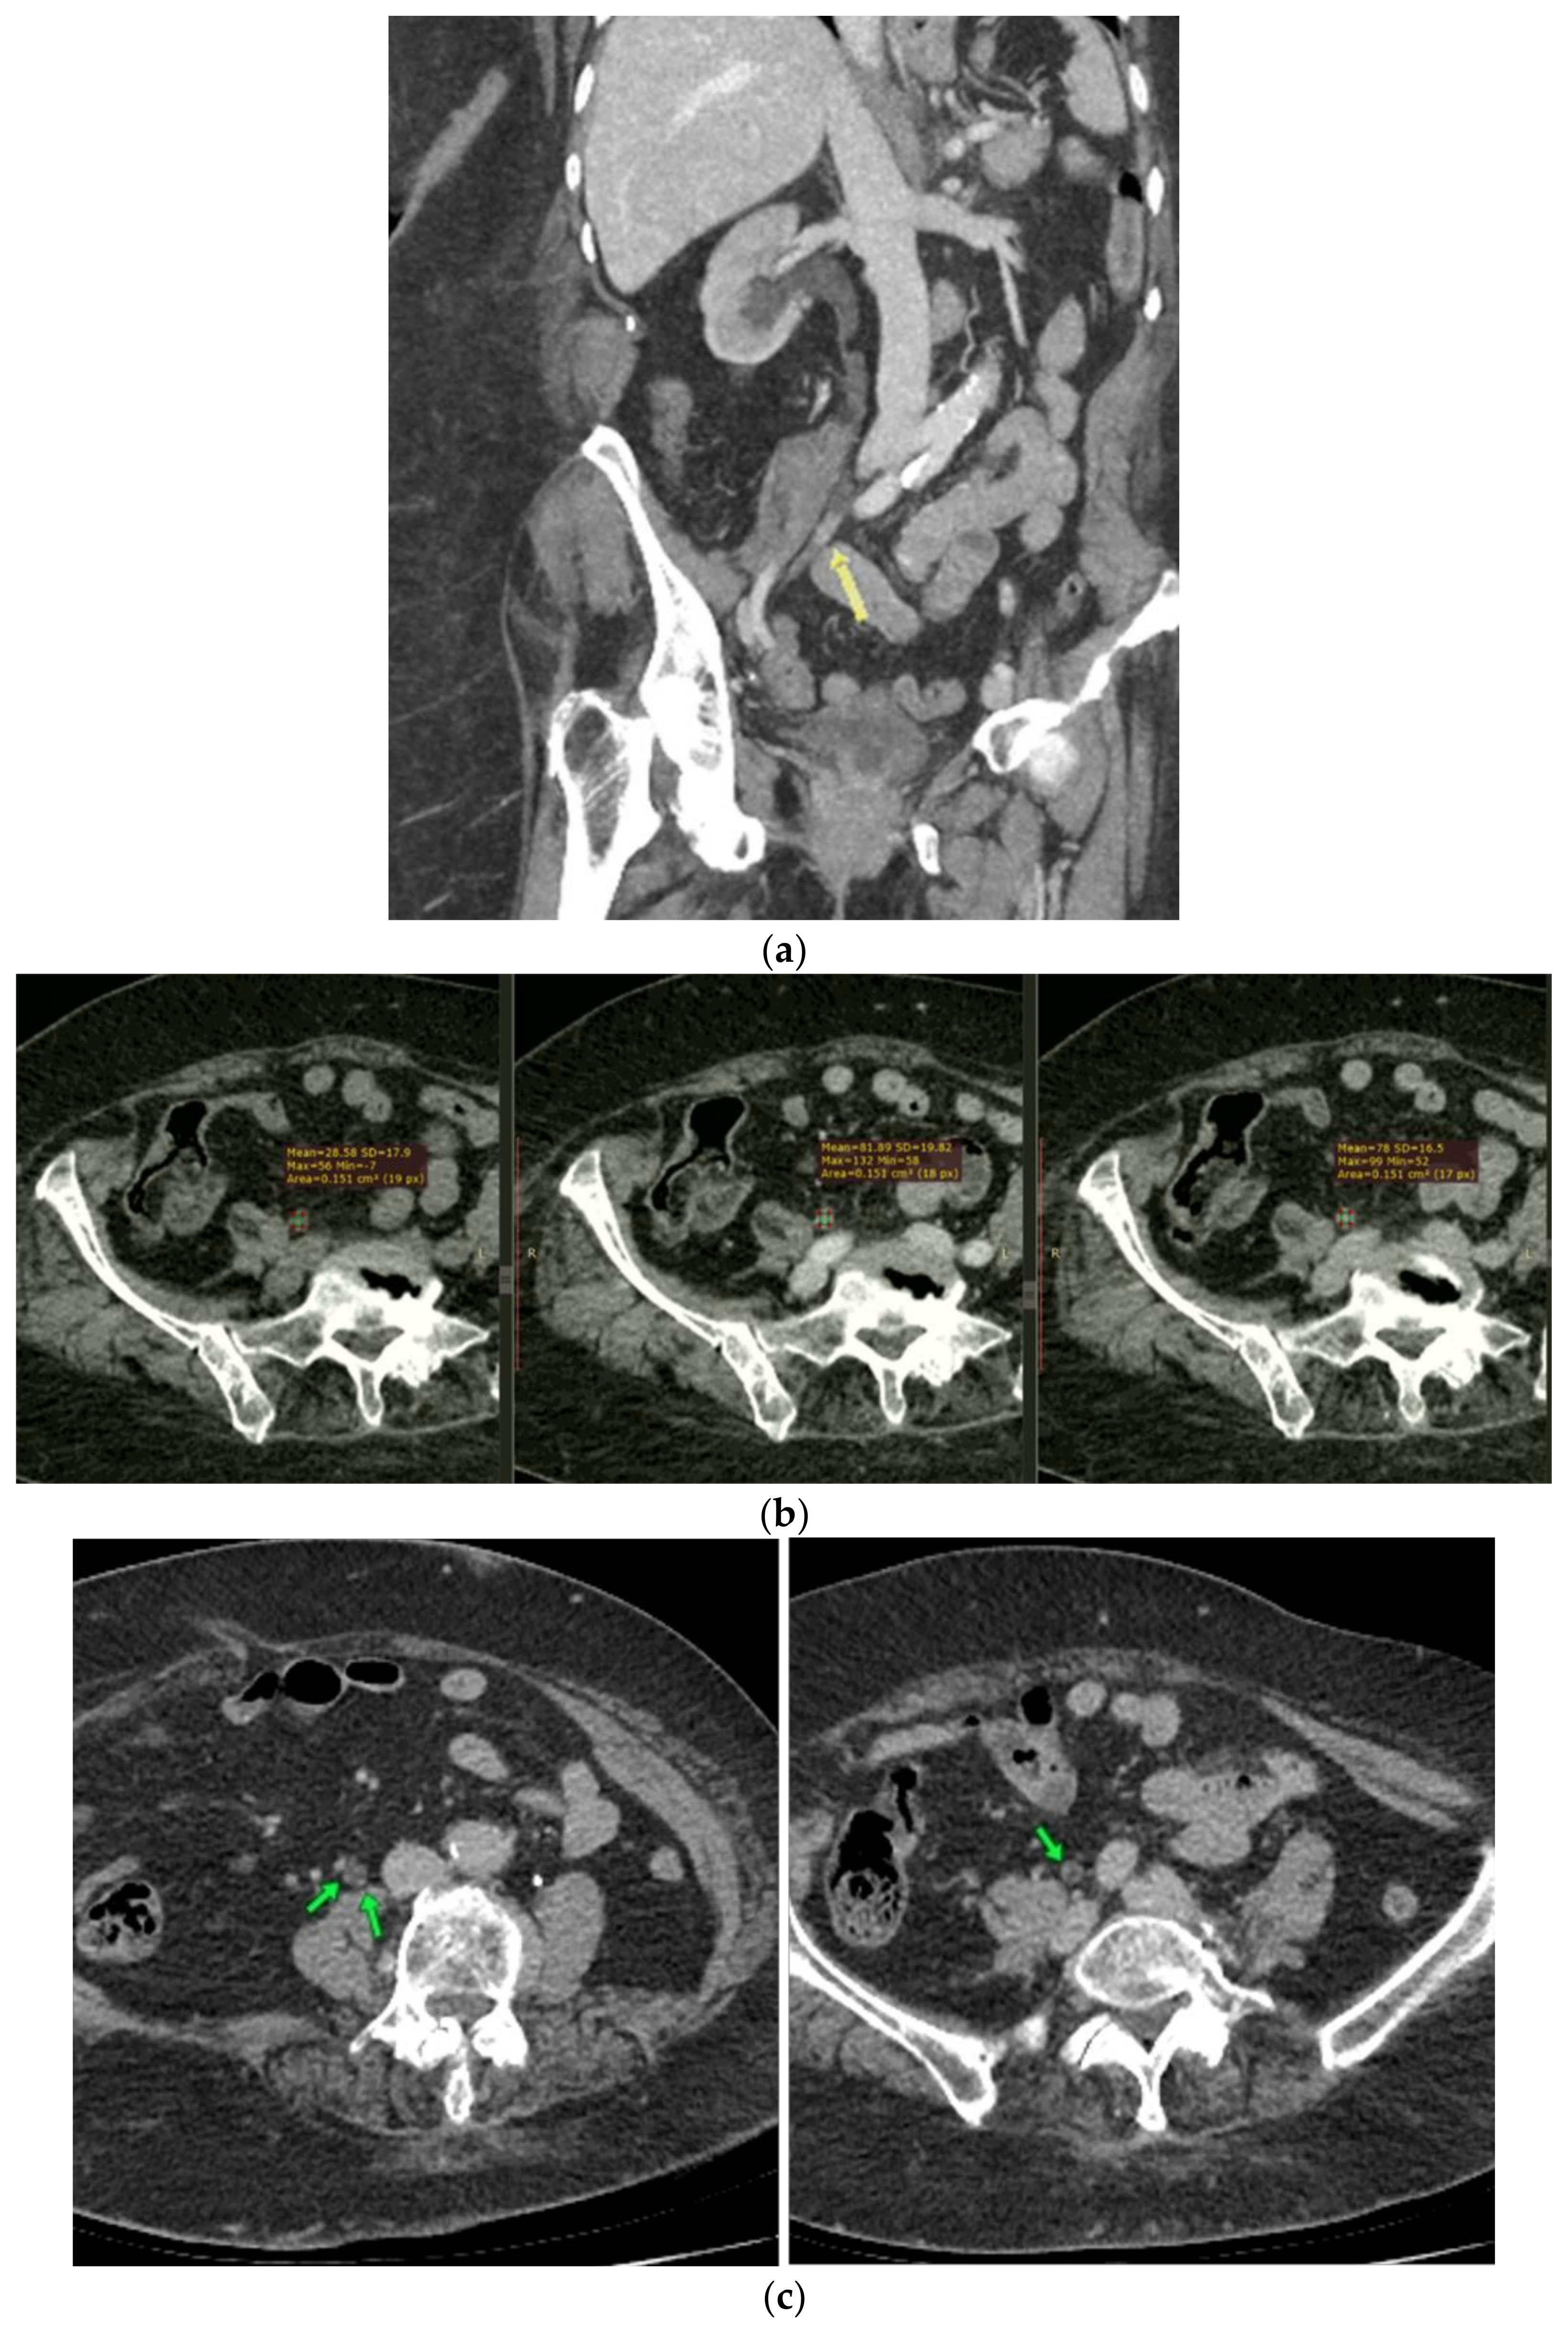

2. Case Report